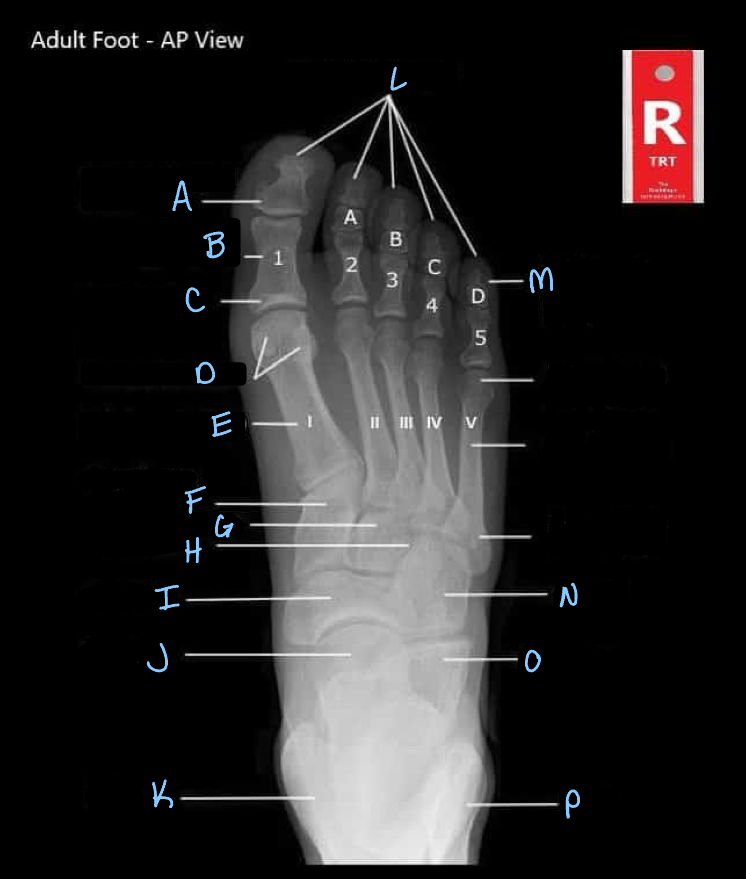

What is A?

interphalangeal joint

16

What is B?

proximal phalanges

17

What is C?

metatarsophalangeal joints

18

What is D?

sesamoid bones

19

What is E?

20

Q

A

21

What is G?

intermediate cuneiform

22

What is H?

lateral cuneiform

23

What is I?

24

25

What is K?

tibia

26

What is L?

distal phalanges

27

What is M?

intermediate phalanges

28

What is N?

cuboid

29

What is O?

calcaneum

30

What is P?

fibula